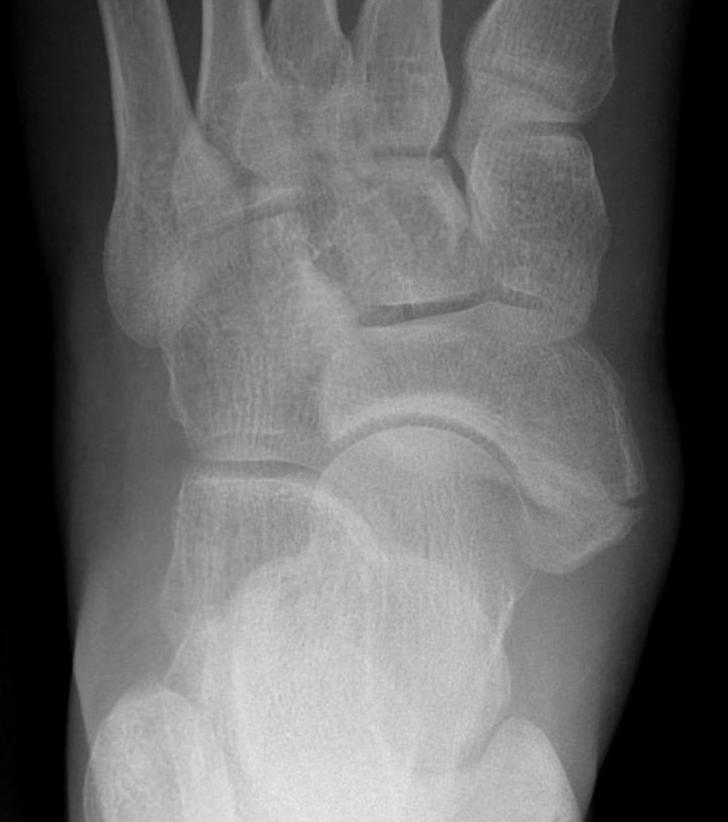

Classification

| Type I | Type II | Type III |

|---|---|---|

|

Small ossicle proximal to insertion In the Tibialis posterior tendon |

Triangular ossicle Connected to navicular via syndesmosis May fracture with injury |

Enlarged medial navicular Cornuate navicular Likely that Type II accessory navicular has fused |